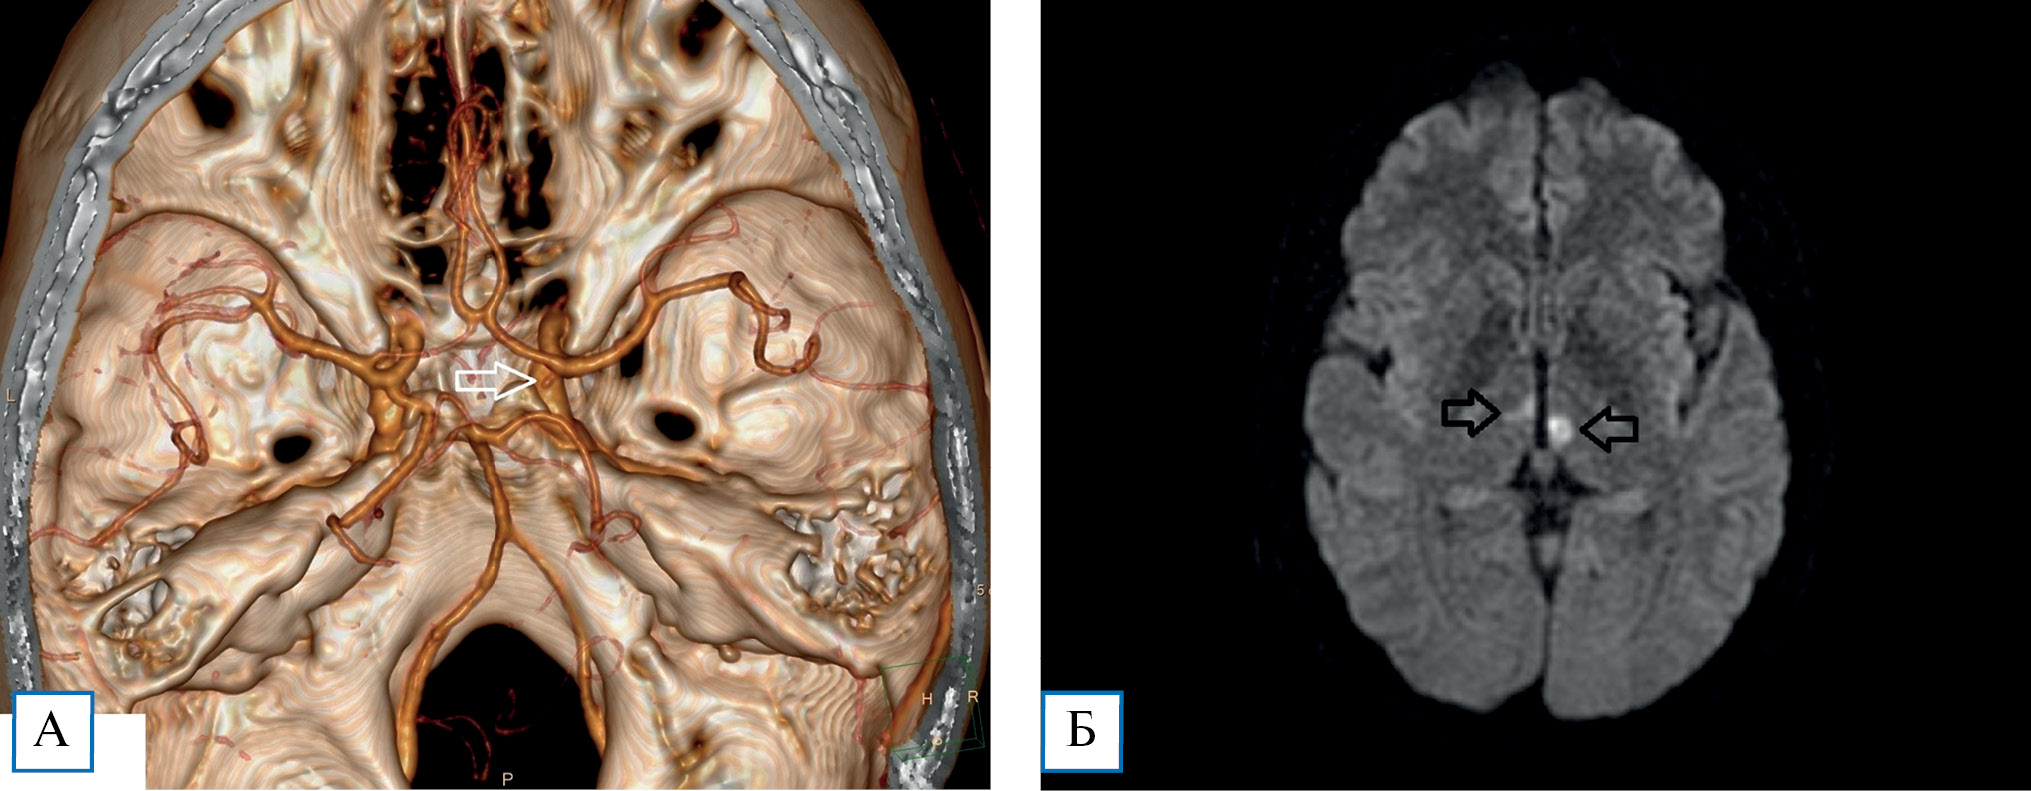

При поступлении выполнены КТ и МРТ головного мозга. При КТ патологии в веществе мозга не выявлено. По результатам спиральной КТ-ангиографии выявлена частичная задняя трифуркация левой внутренней сонной артерии, отхождение правой верхней мозжечковой артерии от Р1-сегмента правой ЗМА и предположительно мешотчатая аневризма А1-сегмента правой переднемозговой артерии (вблизи устья) (рис. 1, А).

Результат МРТ: картина двустороннего острого лакунарного инфаркта в парамедиальных отделах обоих таламусов (слева до 6 мм, справа до 4,5 мм), инфаркт в бассейне артерии Першерона (рис. 1, Б).

Рис. 1. Пациентка К., 43 года, с инфарктом головного мозга в вертебрально-базилярном бассейне (артерия Першерона): результаты обследования

Примечание. А — спиральная КТ-ангиография головного мозга с 3D-реконструкцией (стрелкой показана мешотчатая аневризма правой переднемозговой артерии, предположительно); Б — МРТ головного мозга, режим DWI (стрелками показаны лакунарные очаги острой ишемии в парамедиальных отделах таламусов)